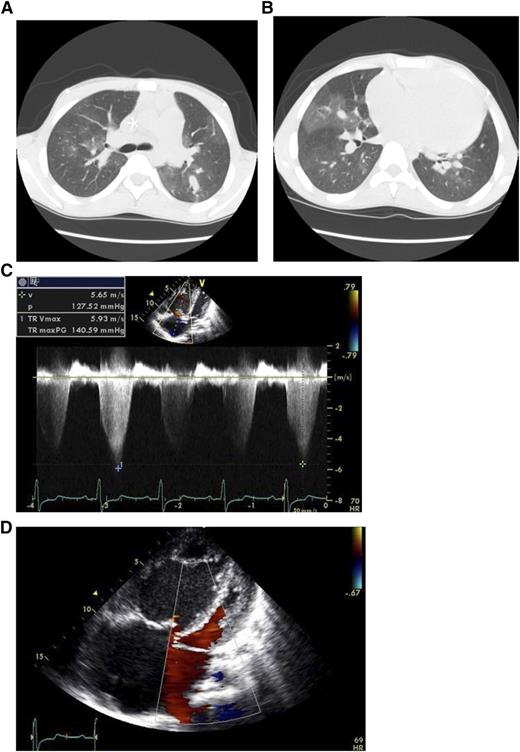

Patient case: An 18-year-old male patient with homozygous hemoglobin SS disease was evaluated for progressive dyspnea and elevated tricuspid regurgitant jet velocity (TRV) on echocardiography. The patient’s case is described in detail in Lancet.1 He had been treated with regular transfusions since childhood for stroke, had rare episodes of vaso-occlusive pain episodes, and did not take narcotic pain medications. He presented with progressive severe dyspnea on exertion and lower extremity edema. His laboratory tests were notable for a total hemoglobin level of 11.8 g/dL and hemoglobin S levels <30% but with 18% reticulocytes and elevated markers of hemolysis, such as high plasma levels of lactate dehydrogenase, aspartate amino transferase, and indirect bilirubin. The computed tomography scan of his chest in Figure 1A-B shows a large pulmonary artery, which has a greater diameter than his aorta, and a mosaic perfusion pattern, typical for severe pulmonary arterial hypertension. His Doppler echocardiographic study (Figure 1C) showed an unusually high TRV of 5.93 m/s, consistent with a calculated pulmonary artery systolic pressure of >140 mm Hg (4 times the TRV squared = 4V2). Additional images in Figure 1D show a dilated right ventricle and right atrium with a compressed left ventricle. The patient’s right heart catheterization revealed a pulmonary artery systolic pressure of 147 mm Hg and diastolic pressure of 49 mm Hg; note that the normal values are ∼25/10 mm Hg.

Imaging from an 18-year-old male patient with homozygous hemoglobin SS disease. (A,B) CT scan demonstrating large pulmonary artery and mosaic perfusion pattern due to areas of higher radiodensity where the blood flow is high (more white), next to darker areas where the pulmonary arterioles are narrowed and blood flow is reduced. (C) Doppler echocardiographic study records a very high tricuspid regurgitant jet velocity (TRV) of 5.93 m/s, which estimates a pulmonary artery systolic pressure of greater than 140 mm Hg. (D) Four-chamber view of his heart shows shows a dilated right ventricle (RV) and right atrium (RA) with a compressed left ventricle (LV).

Imaging from an 18-year-old male patient with homozygous hemoglobin SS disease. (A,B) CT scan demonstrating large pulmonary artery and mosaic perfusion pattern due to areas of higher radiodensity where the blood flow is high (more white), next to darker areas where the pulmonary arterioles are narrowed and blood flow is reduced. (C) Doppler echocardiographic study records a very high tricuspid regurgitant jet velocity (TRV) of 5.93 m/s, which estimates a pulmonary artery systolic pressure of greater than 140 mm Hg. (D) Four-chamber view of his heart shows shows a dilated right ventricle (RV) and right atrium (RA) with a compressed left ventricle (LV).